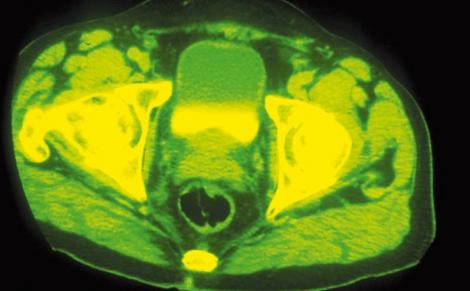

L'INCIDENCE du cancer de la prostate est en augmentation en Europe avec, en tête des pays touchés, la Suède où il frappe 90 hommes sur 100 000. La France arrive en 6e position avec 60 hommes atteints sur 100 000. Les pays en développement ne sont pas épargnés. Il reste la deuxième principale cause de décès due au cancer, tuant 221 000 hommes chaque année dans le monde. C'est dire l'intérêt d'une prise en charge précoce et du développement de nouvelles options thérapeutiques pour combattre les tumeurs. La classe des bloqueurs de GnRH est l'une d'entre elles et le Degarelix, peptide synthétique développé par Ferring, appartient à cette classe. Son originalité : freiner rapidement la production de la testostérone et éviter la stimulation de la testostérone et le risque de flambée tumorale. Le Degarelix a fait l'objet d'un vaste programme clinique dans le cadre de plus de 20 études.

L'étude de phase III randomisée, ouverte, en groupes parallèles, présentée lors de l'Association européenne d'urologie (EAU Milan) a porté sur des patients atteints d'un cancer de la prostate et suivis pendant 12 mois.

L'administration mensuelle du Degarelix a été comparée avec celle de leuproréline (7,5 mg), un agoniste de la GnRH. Une réduction significative des taux sériques de testostérone et d'antigènes prostatiques a été observée avec le Degarelix, et ce de façon beaucoup plus rapide qu'avec l'autre produit : au 3e jour de l'étude, le taux de testostérone était inférieur ou égal à 0,5 ng/ml chez 96,1 % des patients du bras Degarelix, contre 0 % dans l'autre bras. A J14, tous les patients sous Degarelix avaient un taux de testostérone inférieur ou égal à 0,5 ng/ml contre seulement 18,2 % des patients de l'autre bras. De plus, le Degarelix a montré un effet durable puisqu'il a été en mesure de maintenir ces taux à un niveau faible durant les 12 mois de l'étude. Les deux traitements ont été bien tolérés avec un profil de tolérance similaire.

Ces nouvelles données montrent que le Degarelix agit d'une manière extrêmement rapide sur le taux de testostérone, proche de l'effet immédiat obtenu par chirurgie (orchidectomie) mais sans en avoir les effets physiques et psychologiques négatifs. Degarelix apparaît ainsi comme une option thérapeutique très prometteuse chez les hommes atteints d'un cancer de la prostate. En février 2008, une demande d'autorisation de mise sur le marché de Degarelix a été soumise par Ferring à la FDA et à l'Agence européenne du médicament.